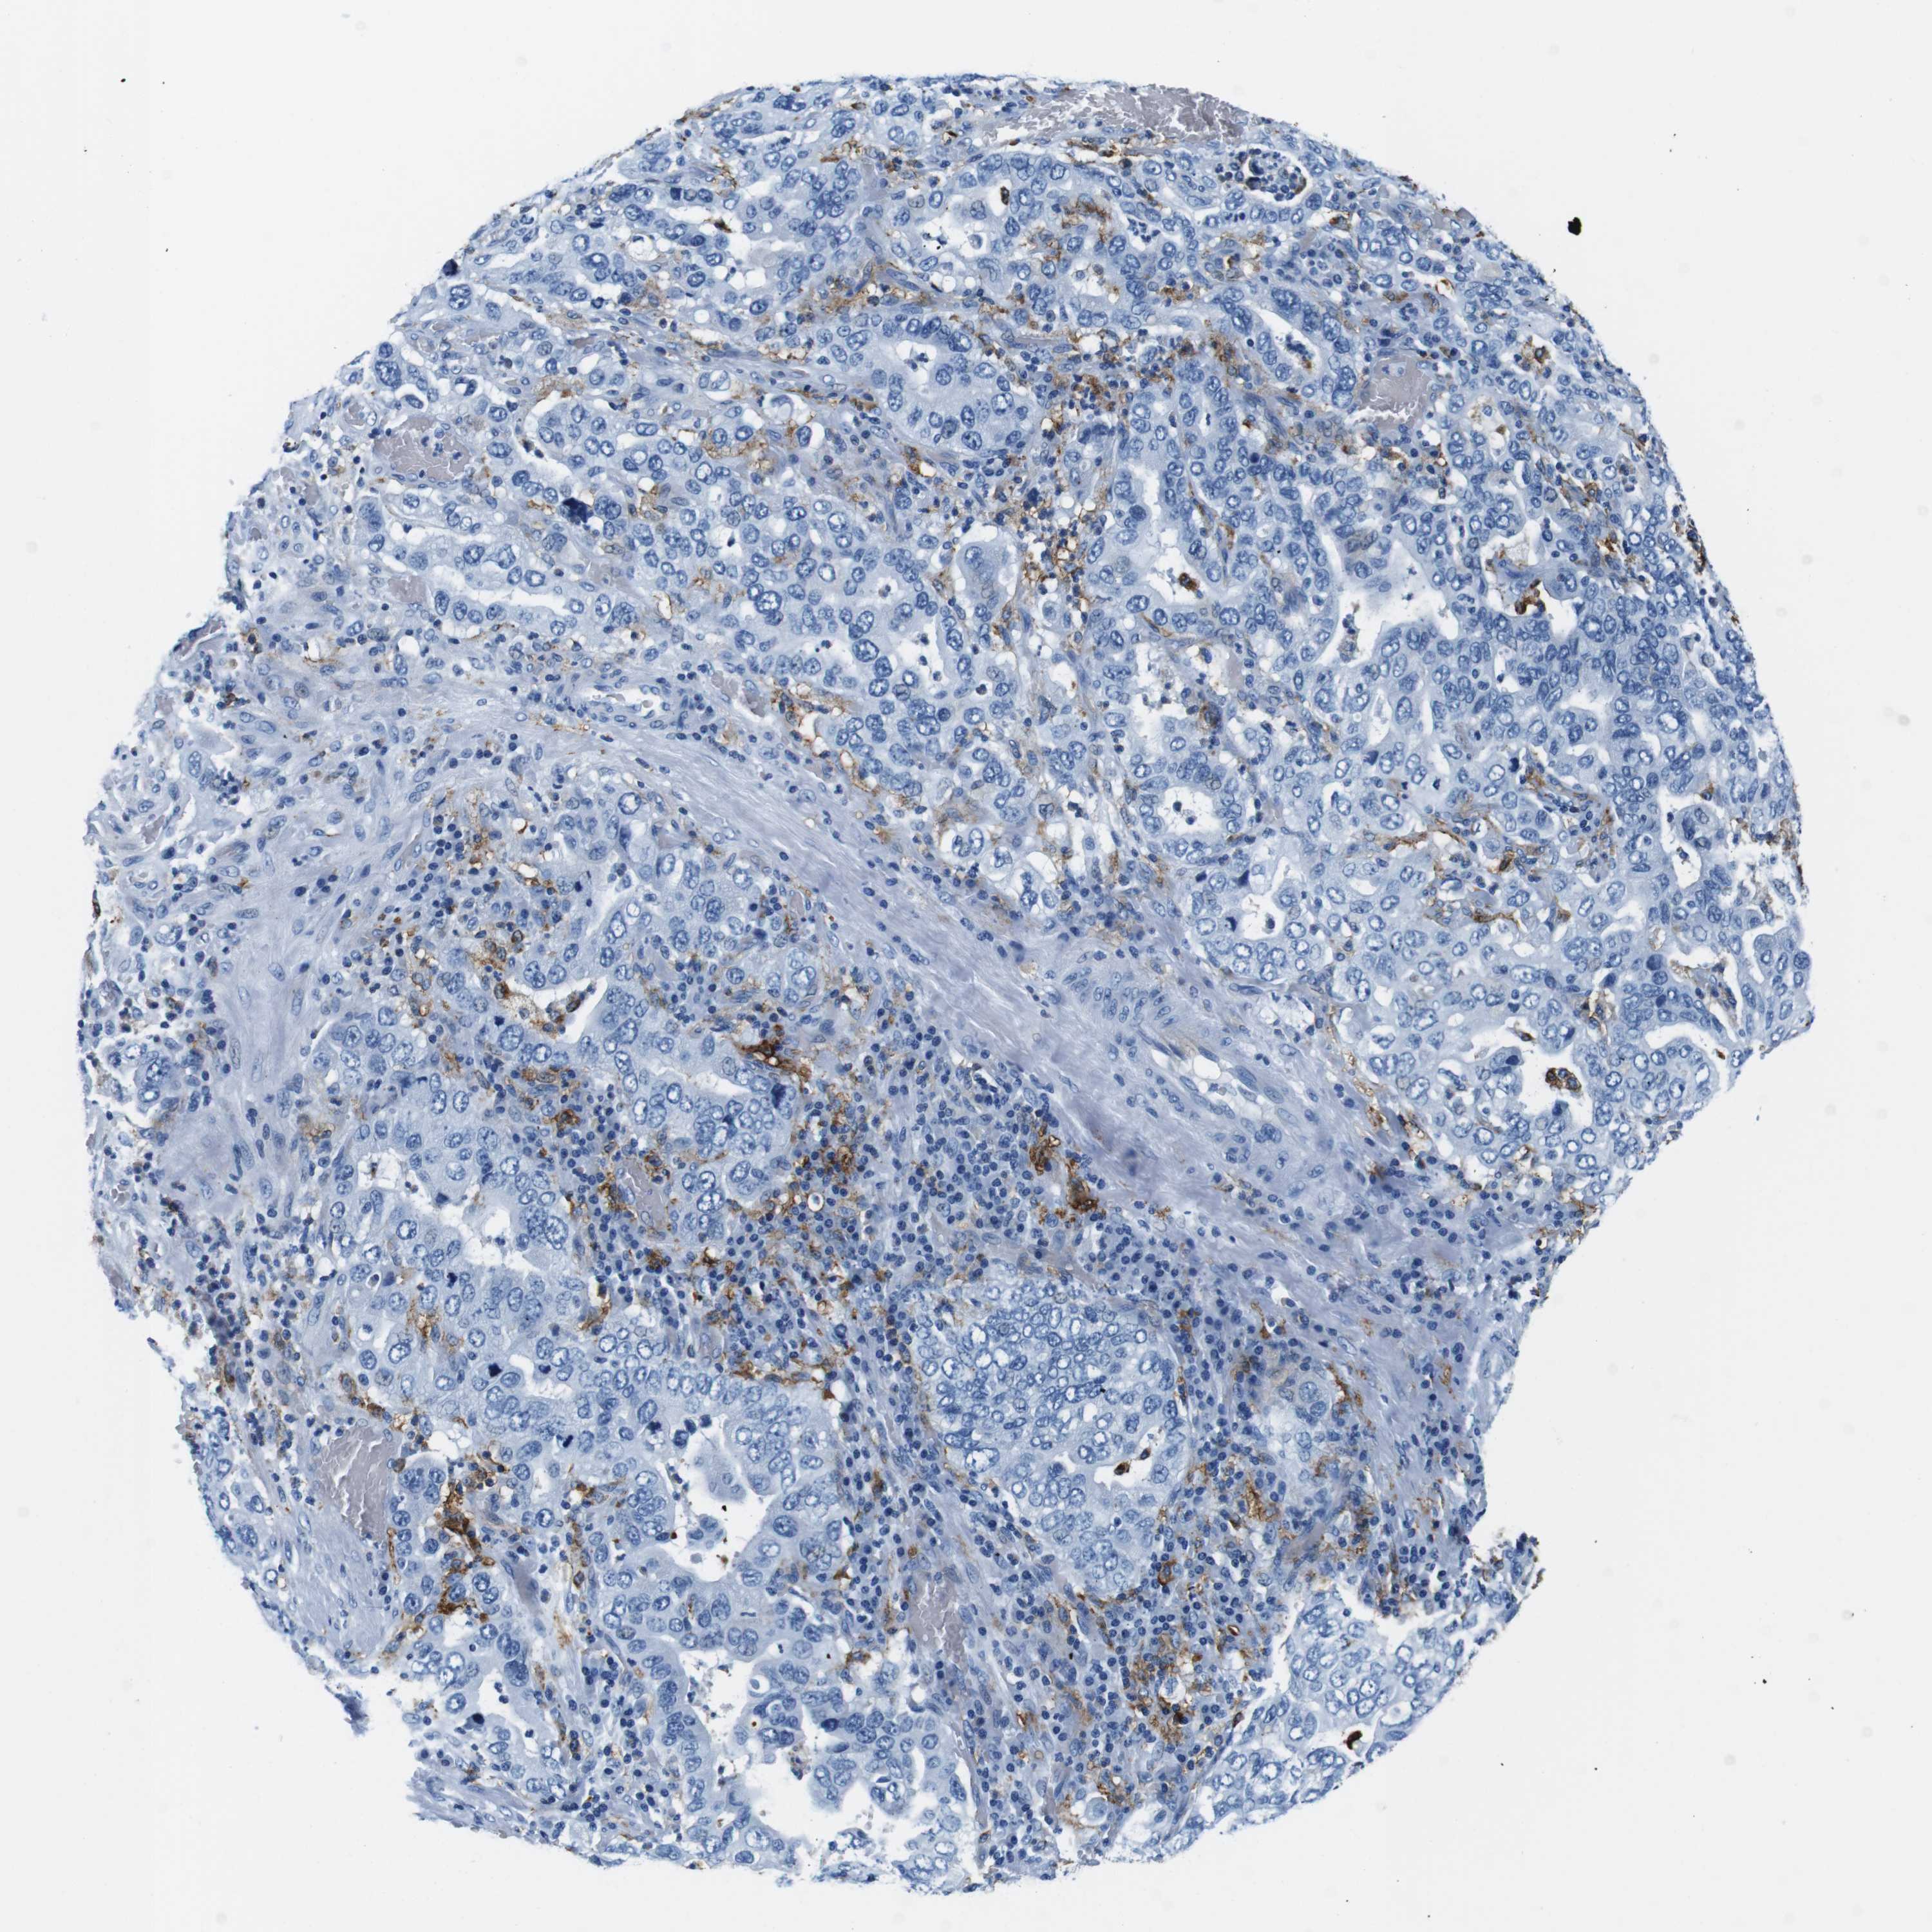

STOMACH CANCER - Protein expressioni

A mouse-over function shows sample information and annotation data. Click on an image to view it in a full screen mode. Samples can be filtered based on level of antibody staining by selecting one or several of the following categories: high, medium, low and not detected. The assay and annotation is described here.

Note that samples used for immunohistochemistry by the Human Protein Atlas do not correspond to samples in the TCGA dataset.

Antibody stainingi

Antibody staining in the annotated cell types in the current human tissue is reported as not detected, low, medium, or high, based on conventional immunohistochemistry profiling in selected tissues. This score is based on the combination of the staining intensity and fraction of stained cells.

Each image is clickable and will lead to virtual microscopy that enables deeper exploration of all samples and also displays staining intensity scores, fraction scores and subcellular localization as well as patient and tissue information for each sample.

Antibody HPA043151

Antibody CAB015400

Antibody CAB034021

Staining

High

Medium

Low

Not detected

Intensity

Strong

Moderate

Weak

Negative

Quantity

>75%

75%-25%

<25%

None

Location

Nuclear

Cytoplasmic/membranous

Cytoplasmic/membranous,nuclear

Adenocarcinoma, NOS